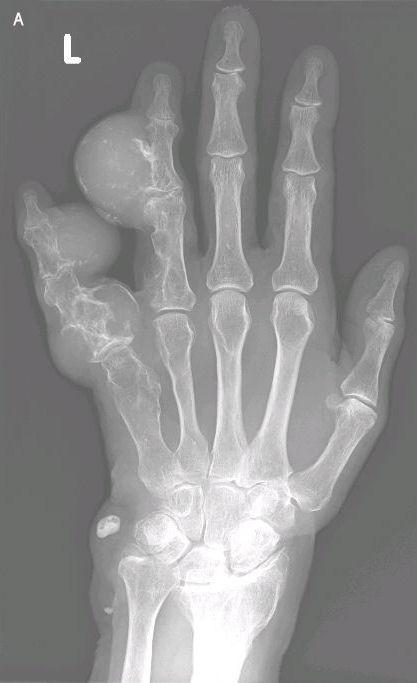

Een vrouw met multipele zwellingen aan de linker hand

Een 66-jarige vrouw bezocht de polikliniek Orthopedie met enkele bolvormige, beenharde, pijnloze zwellingen aan de linker ringvinger en pink. Deze waren haar hele leven al aanwezig geweest, maar de laatste jaren waren zij duidelijk groter worden en gaven zij lichte bewegingsbeperkingen van de vingers. Daarnaast waren er multipele hemangiomen zichtbaar op haar linker voet, rechter hand en beide polsen en had zij een beenlengteverschil van 5 cm ten nadele van het linker been.